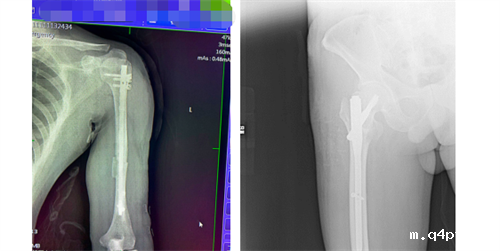

股骨颈骨折、早期股骨头坏死保髋治疗

老龄骨质疏松性股骨转子间骨折综合治疗